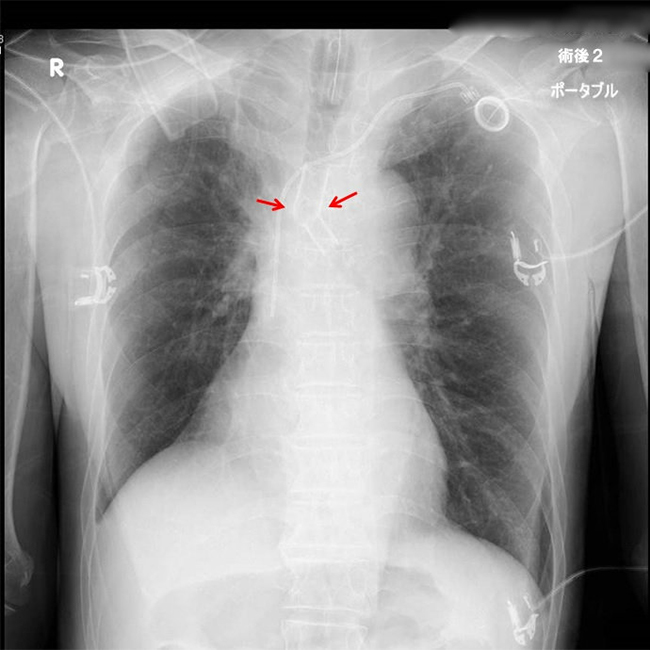

がんや結核後遺症などが原因で気管支内腔が狭くなり呼吸が苦しくなった場合にステント留置術が行われることがあります。メスを用いることなく呼吸困難を解消することが目的です。軟性または硬性の気管支鏡を用いて気道内にステントを挿入し狭くなった気管・気管支を拡張します。レーザー治療や風船による拡張術が併用されることもあります。通常の麻酔や気道確保が困難な場合は、麻酔科医・臨床工学士・呼吸器内科医など多くのスタッフと協力して一時的な体外式膜型人工肺(ECMO・エクモ)も併用して安全確実に手術を行います。